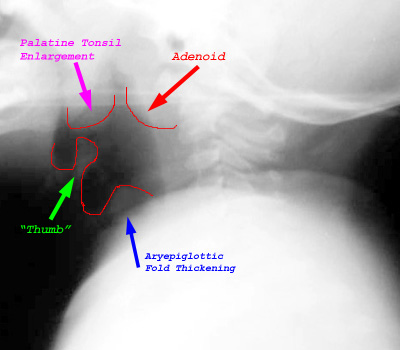

Intubation may be necessary to maintain the airway, so it is best not to take the patient out of the emergency department for imaging. If imaging is obtained, a lateral soft tissue neck film should be taken in an upright position. The hypopharynx will be enlarged with thickening of the epiglottis and aryepiglottic folds. The thickening of the epiglottis results in the "thumb sign". Subglottic edema, as seen in croup, will also be found in 25% of patients with epiglottitis. | |

| Lateral soft tissue demonstrates thickening of aryepiglottic folds and the epiglottis ("thumb sign"). Also note the enlargement of the palatine tonsil. |